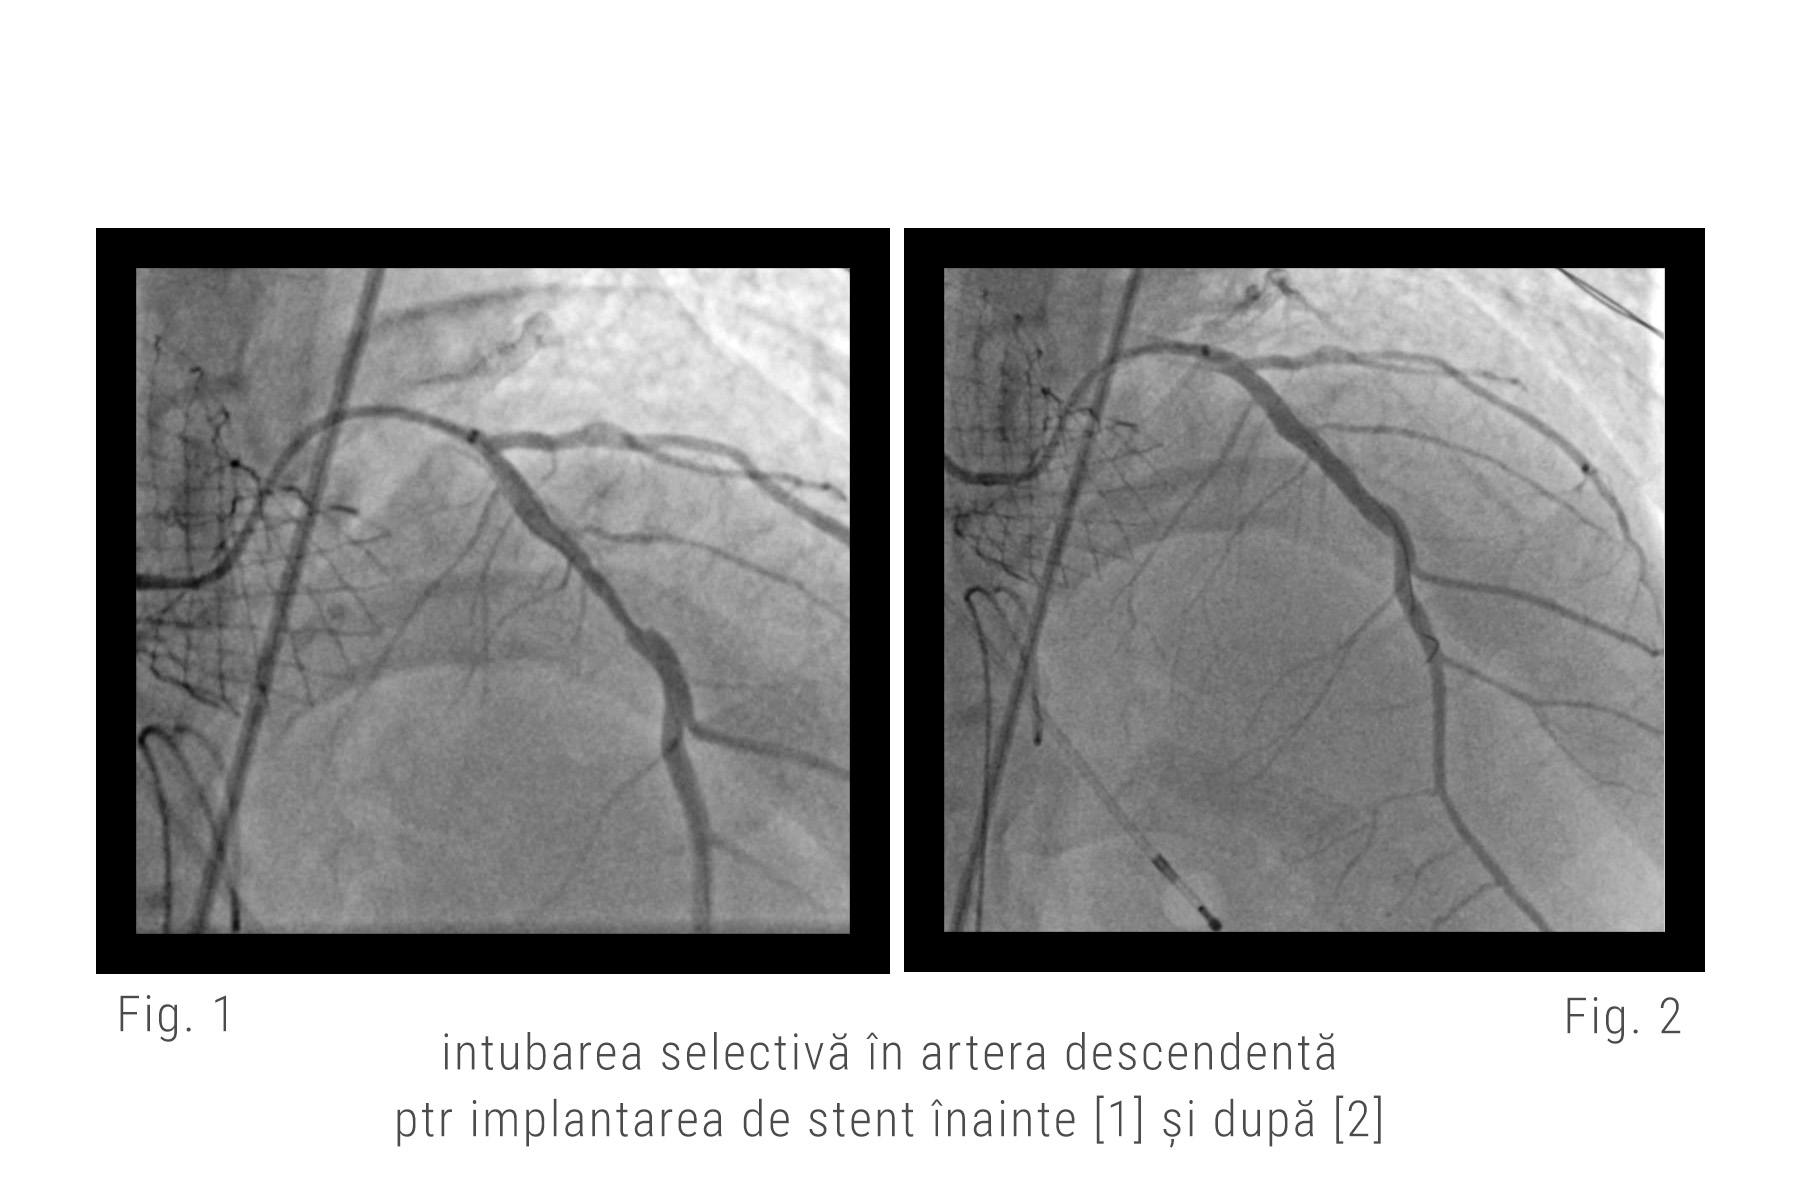

Echipa noastră de medici a decis să rezolve cazul prin implantarea mai întâi a unei valve autoexpandbile Evolute ProPlus (Medtronic), pentru a ușura sarcina inimii de a ejecta sângele (decizie care s-a dovedit corectă, pentru că după implantare s-a observat imediat o ameliorare a contractilității, cu o creștere a fracției de ejecție la 30%). A urmat apoi, în continuarea intervenției, revascularizarea arterelor coronare cu ajutorul unui artificiu tehnic prin care s-a folosit o extensie pentru cateterul standard cu care au putut fi canulate selectiv ambele ramuri ale arterei coronare stângi pentru a implanta cu succes stenturile.